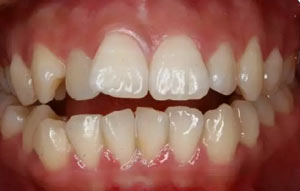

矯治結(jié)束后口內(nèi)像

治療前后口內(nèi)相對(duì)比